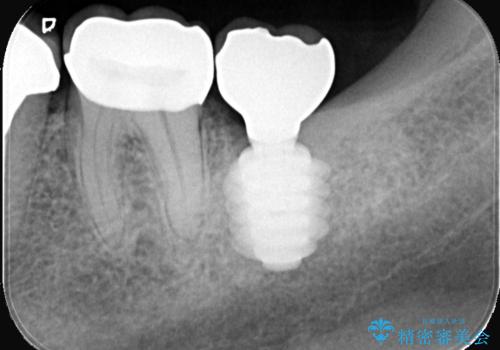

保存は困難と判断し、左下7番は抜歯即時インプラントによる治療を行いました。

抜歯と同時にインプラントを埋入するため、歯茎を切開する必要がなく、術後の痛みが出にくい治療方法です。

手術は1回で完了し、被せ物を装着するまでの治療期間も約3か月と、身体的・時間的な負担を抑えることができます。